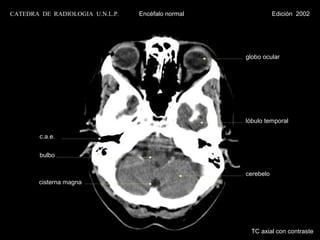

globo ocular

lóbulo temporal

c.a.e.

bulbo

cerebelo

cisterna magna

TC axial con contraste